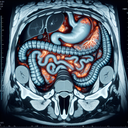

МРТ шлунка

Магнітно-резонансна томографія (МРТ) шлунка — це неінвазивний діагностичний метод, який використовує магнітні поля та радіохвилі для отримання детальних зображень органів черевної порожнини. Наведу основну інформацію про процедуру: 1. **Показання до МРТ шлунка**: - Підозра на новоутворення в шлунку...